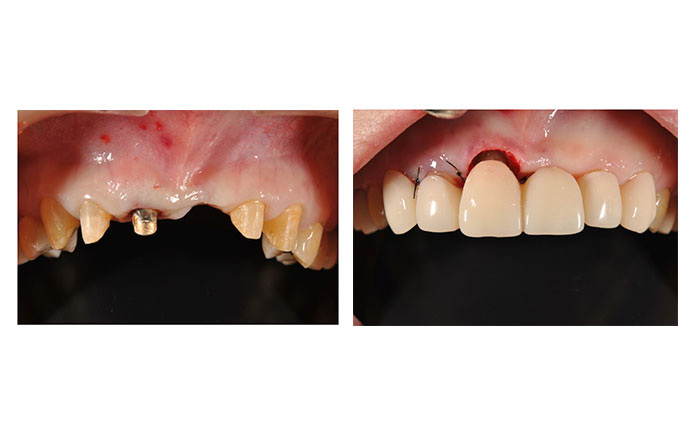

4.被せ物を被せられるようにする、歯冠長延長術

歯冠長延長術は、クラウンレングスニングとも呼ばれます。

歯冠長延長術は3と同様に、被せ物をする予定の歯に対して行います。

被せ物が合っていなかったり、歯ぐきの下にむし歯があると、歯周病が悪化する場合があります。

そのため、歯ぐきと骨を整えて、歯ぐきの下のむし歯の除去を行い、ピッタリと合う被せ物を被せられる状態に改善を行います。

1)歯冠長延長術のメリット

・歯ぐきの下のむし歯が除去できる

・抜歯しなくて良い可能性が増える

・見た目が改善する場合がある

2)歯冠長延長術のデメリット

・歯がしみやすくなる可能性がある

・見た目が悪くなる場合がある